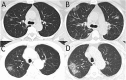

Radiologic characteristics of 2019 novel coronavirus (2019-nCoV) infected pneumonia (NCIP) which had not been fully understood are especially important for diagnosing and predicting prognosis. We retrospective studied 27 consecutive patients who were confirmed NCIP, the clinical characteristics and CT image findings were collected, and the association of radiologic findings with mortality of patients was evaluated. 27 patients included 12 men and 15 women, with median age of 60 years (IQR 47-69). 17 patients discharged in recovered condition and 10 patients died in hospital. The median age of mortality group was higher compared to survival group (68 (IQR 63-73) vs 55 (IQR 35-60), P = 0.003). The comorbidity rate in mortality group was significantly higher than in survival group (80% vs 29%, P = 0.018). The predominant CT characteristics consisted of ground glass opacity (67%), bilateral sides involved (86%), both peripheral and central distribution (74%), and lower zone involvement (96%). The median CT score of mortality group was higher compared to survival group (30 (IQR 7-13) vs 12 (IQR 11-43), P = 0.021), with more frequency of consolidation (40% vs 6%, P = 0.047) and air bronchogram (60% vs 12%, P = 0.025). An optimal cutoff value of a CT score of 24.5 had a sensitivity of 85.6% and a specificity of 84.5% for the prediction of mortality. 2019-nCoV was more likely to infect elderly people with chronic comorbidities. CT findings of NCIP were featured by predominant ground glass opacities mixed with consolidations, mainly peripheral or combined peripheral and central distributions, bilateral and lower lung zones being mostly involved. A simple CT scoring method was capable to predict mortality.